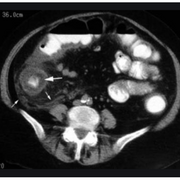

Appendicitis?